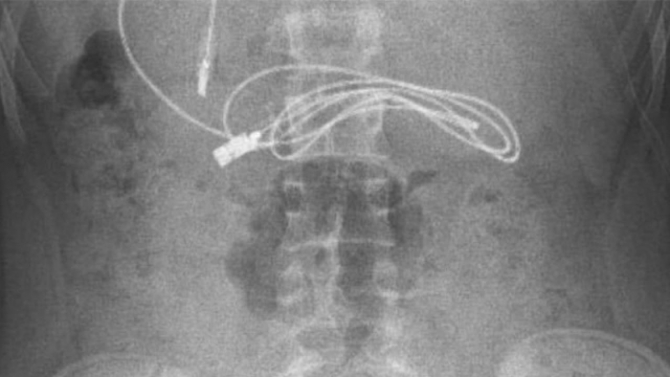

Diyarbakır'da kusma ve bulantı şikayetiyle hastaneye giden 15 yaşındaki erkek çocuğunun çekilen röntgeninde, midesinde şarj kablosu ve toka olduğu tespit edildi.

Ameliyatı gerçekleştiren Prof. Dr. Yaşar Doğan, kablonun bir ucunun ince bağırsağa geçmesi nedeniyle zorlandıklarını ifade ederek, “Hastanın kusma ve karın ağrısı şikayetleri olması üzerine sağlık kuruluşuna başvurulmuş. Orada yapılan incelemelerde hastanın midesinde kablo tespit edilmesi üzerine bize danışıldı. 112 aracılığıyla hastaya gerekli işlemi yapıp yapmayacaklarını bize sordular. Biz de hastayı bize gönderebileceklerini kendilerine ilettik. Hasta bize geldikten sonra ön hazırlık yapıldı ve gerekli olan açlık süresinin ardından hastaya endoskopik işlem yapıldı. Endoskopik işlemle midedeki kablo çıkarıldı. Kabloyu çıkarırken açıkçası zorlandık, çünkü kablonun bir ucu ince bağırsağa geçmişti. İşlem başarılı bir şekilde sonlandırıldıktan sonra hasta sağlıklı bir şekilde evine gönderildi” dedi.